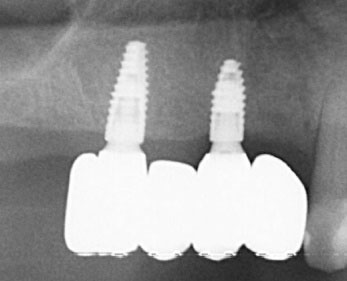

The patients were recalled at least once a year to assess the restorations functionally and aesthetically, peri-implant tissues, and implant health status. An individual maintenance program with regular dental hygiene sessions was performed for every patient during the entire study period, and an x-ray was taken at the 2-year follow-up. - show the workflow for one exemplary clinical case treated with one mesial cantilever implant-retainer FPP replacing missing lateral to posterior teeth.

Figure 6. Periapical radiograph of the implant at two years follow up